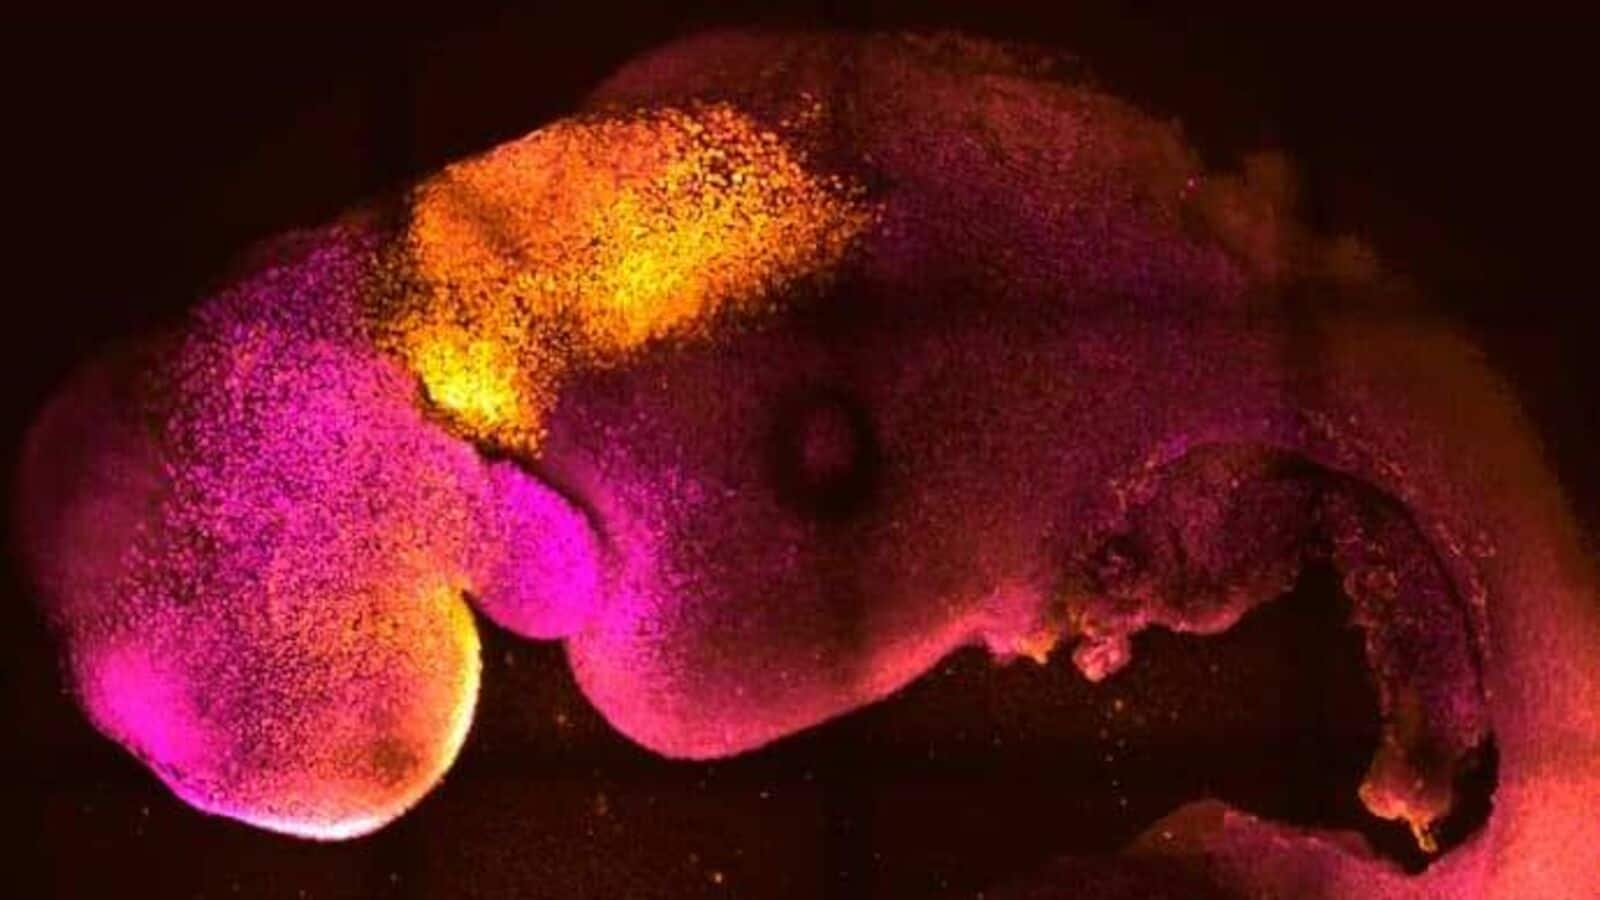

Live Tech News : Human Embryos Grown In Lab For Longer Than Ever Before

www.livetechnews.comhuman embryos lab grown embryo

www.livetechnews.comhuman embryos lab grown embryo